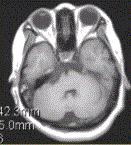

问题 患者女,41岁。右侧面肌抽搐。MRI显示如下图。 关于表皮样囊肿与蛛网膜囊肿的鉴别诊断,正确的是

选项 A.表皮样囊肿为CSF样囊性肿块,包绕邻近血管、神经 B.表皮样囊肿形态不规则,肿瘤沿蛛网下腔蔓延,“见缝就钻”为其特点 C.蛛网膜囊肿FLAIR、DWI低信号 D.表皮样囊肿边界清,形态规则 E.蛛网膜囊肿FLAIR、DWI高信号 F.表皮样囊肿FLAIR、DWI高信号

答案 ABCF